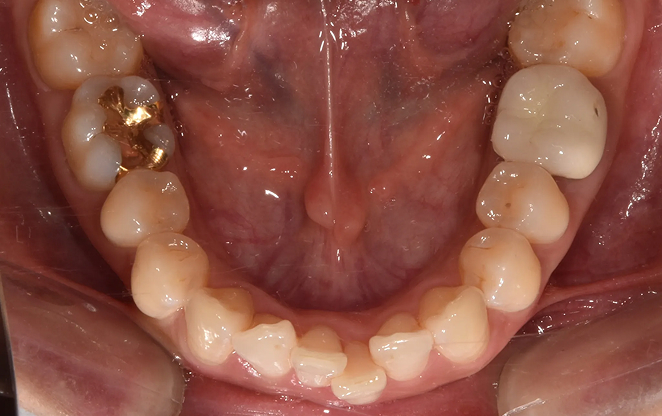

1차 교정

초등학생 1차 교정은 영구치가 나오기 전 혼합치열기에 시작하는

교정입니다. 이 중요한 시기에 치아가 제대로 자리 잡을 수 있도록,

아이의 밝은 미래를 위한 준비를 도와드릴게요.